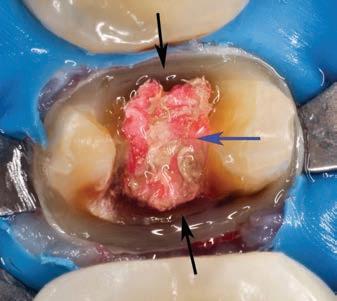

The Use of the DOM in Endodontics

The enhanced vision and illumination of the DOM directly influence the clinician’s field of information in order to make

critical decisions during endodontic treatment. This has a direct effect on outcome and prognosis of the treatment. The following points outlines the importance of magnification during endodontic treatment:

• Identification of structural dentine cracks (Fig.7)

• Diagnosis of secondary caries and leaking restoration margins that can compromise the coronal seal during and after endodontic treatment (Fig.8)

• Preparing more retracted endodontic access cavities (Fig.9)

• Outlining and removing pulp calcifications (Fig.10)

• Identification of missed or additional canal orifices (Fig.11)

• Confirming canal cleanliness after irrigation (Fig.12)

• Managing perforations and tooth resorption lesions (Fig.13)

• Removal of fractured instruments (Fig.14)

• Preparing more conservative osteotomy sites and retrocanal-preparation with ultrasonic instruments for periapical surgery (Fig.15)

Figure 7. Maxillary left first molar of a 54 year old male patient that presented with irreversible pulpitis. After removal of the previous restoration, two structural dentine cracks (black arrows) were noted and stained with methylene blue to follow the extent and depth into the pulp chamber

Figure 8. Mandibular left second premolar after removal of a previously placed crown. Note the secondary caries on the mesial and distal margins (black arrows) and gutta percha (blue arrow) that was exposed to coronal leakage